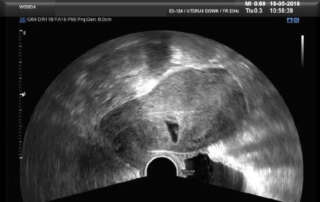

Description of the Endometrium at the different phases of the Menstrual Cycle (A Handout)

DOI: 10.36205/trocar1.2022004